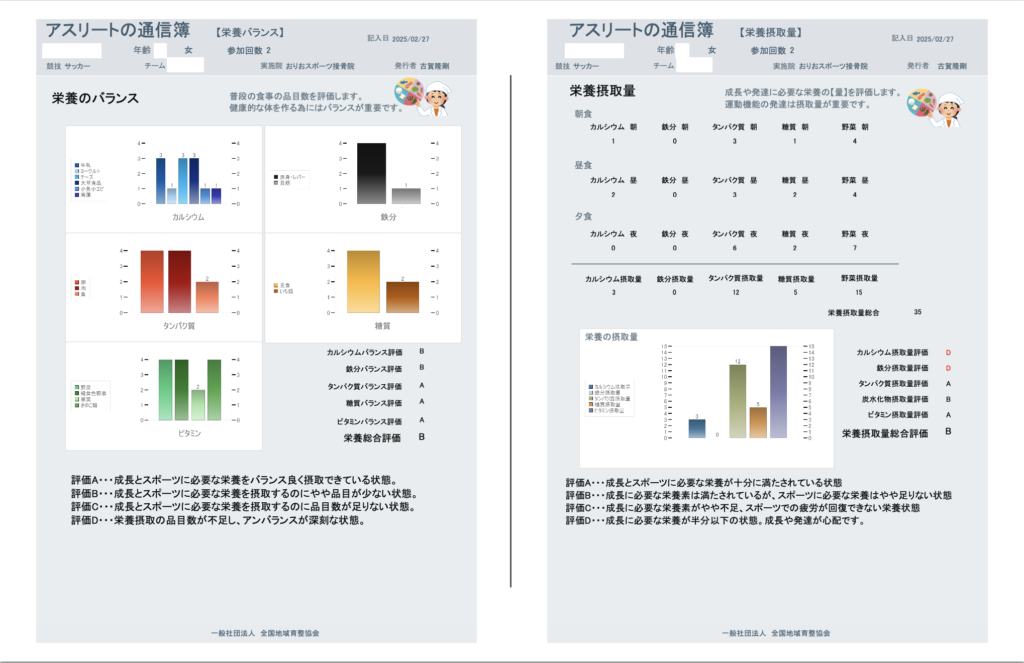

栄養バランス検査で食事を見直す

当院では、「栄養バランス検査(アスリートの通信簿)」という検査を実施しています。これは、お子さんの普段の食事内容を詳しくヒアリングし、どの栄養素が不足しているか、または摂りすぎているかを評価するものです。

検査の結果をもとに、管理栄養士が具体的な食事メニューやレシピを提案します。例えば、「朝食にヨーグルトとバナナを追加しましょう」「夕食の肉の量を増やしましょう」といった、すぐに実践できるアドバイスを行います。

また、お菓子やジュースの摂りすぎ、偏食などの問題がある場合は、改善方法も一緒に考えます。無理なく続けられる食事改善が、長期的な健康とパフォーマンス向上につながります。